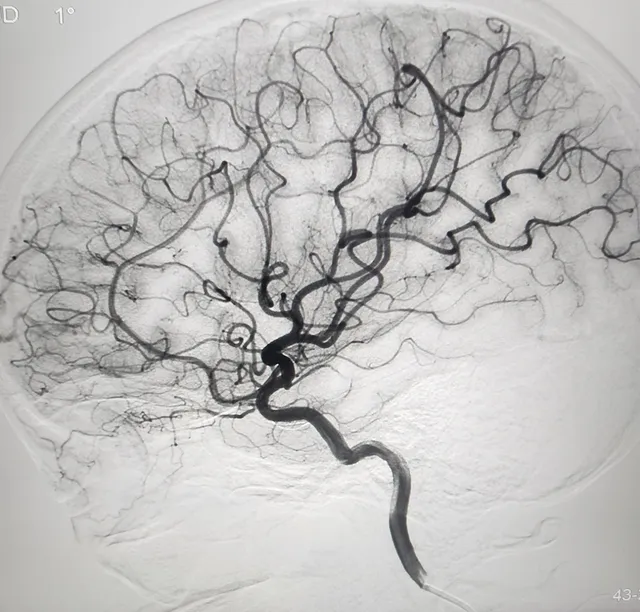

• Lối vào từ động mạch đùi: Bác sĩ luồn ống thông từ động mạch đùi ở vùng bẹn, đi ngược lên theo hệ thống mạch máu để đến não bộ dưới hướng dẫn của máy chụp mạch số hóa xóa nền (DSA).

• Chẩn đoán hình ảnh: Sử dụng hệ thống DSA hiện đại nhất để dựng hình 3D cây mạch máu não, giúp bác sĩ chọn đúng kích thước Coil.